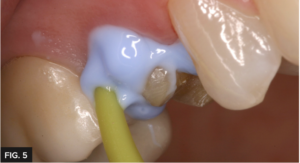

During retraction cord placement, it is crucial to avoid tearing the connective tissue which induces bleeding. To prevent connective tissue damage, light application pressure is used, packing the cord more horizontally while it enters the sulcus. Vertical compaction of the cord with heavier pressure will likely induce bleeding. Following this technique results in adequate tissue retraction without bleeding. Immediately before syringing the Light Body impression material, remove the top retraction cord to allow access to the margin and sulcus. Next, the impression was taken using a Quad- Tray® Xtreme™ metal impression tray with Affinity™ Light Body High Flow and InFlex fast set impression tray material (Clinician’s Choice®). The rigid Quad-Tray Xtreme will not distort due to its aluminum design and low walls. Many dentists choose a flexible plastic impression tray for cost reasons but overlook how plastic trays easily distort, especially in dual-arch impressions. Impression distortion is difficult to observe at the impression stage, however, is often evident at the cementation stage. Inaccurate impressions waste valuable chair time for the dentist and patient with compromised fit and potential issues with longevity. A rigid impression tray coupled with a rigid tray material are essential for eliminating the chance of distortion while maximizing cementation efficiency and overall fit. Affinity Light Body High Flow was injected over the preparation, keeping the placement tip submerged in the material and always moving forward which allows the material to lead the way and results in a bubble-free impression. (FIG. 5)